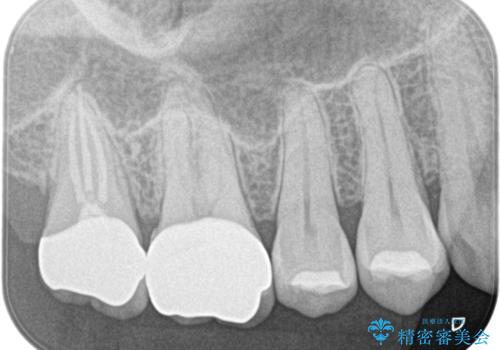

- 左上の奥歯がズキズキ痛い、冷たいものも長引く痛みがあると来院されました。

根管治療を行った後にオールセラミッククラウンにて修復しております。

根管治療を行った場合、破折リスクを軽減するために被せ物を行っております。